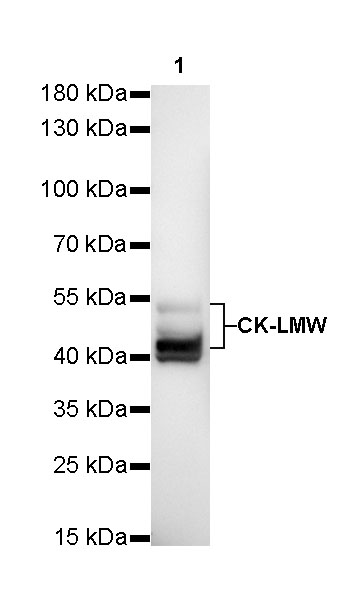

Dilution

| application |

dilution |

species |

| WB |

1:1000 |

|

| IHC-P |

1:500-1:2000 |

|

| IF |

1:500 |

|

Background

CK-LMW is low molecular weight cytokeratins and is expressed in monolayer or glandular epithelium of normal or tumor tissues, such as thyroid, breast, gastrointestinal or respiratory epithelium. It is expressed in adenocarcinoma and the vast majority of nonkeratinizing squamous cell carcinoma, but not in keratinizing squamous cell carcinoma. It combined with CK5/6 for diagnosis of adenocarcinoma and squamous carcinoma.